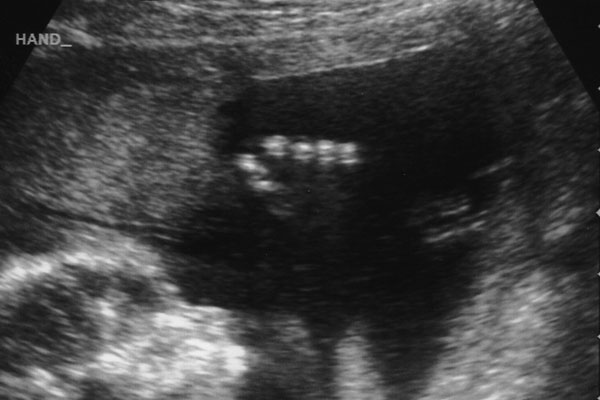

We had our second ultrasound appointment today at 18 weeks. Lindsey and I enjoyed getting to see our baby again. It was amazing to see how much he’s grown since our last ultrasound five weeks ago. Oh, did we mention it’s a he?

Tiny fingers.